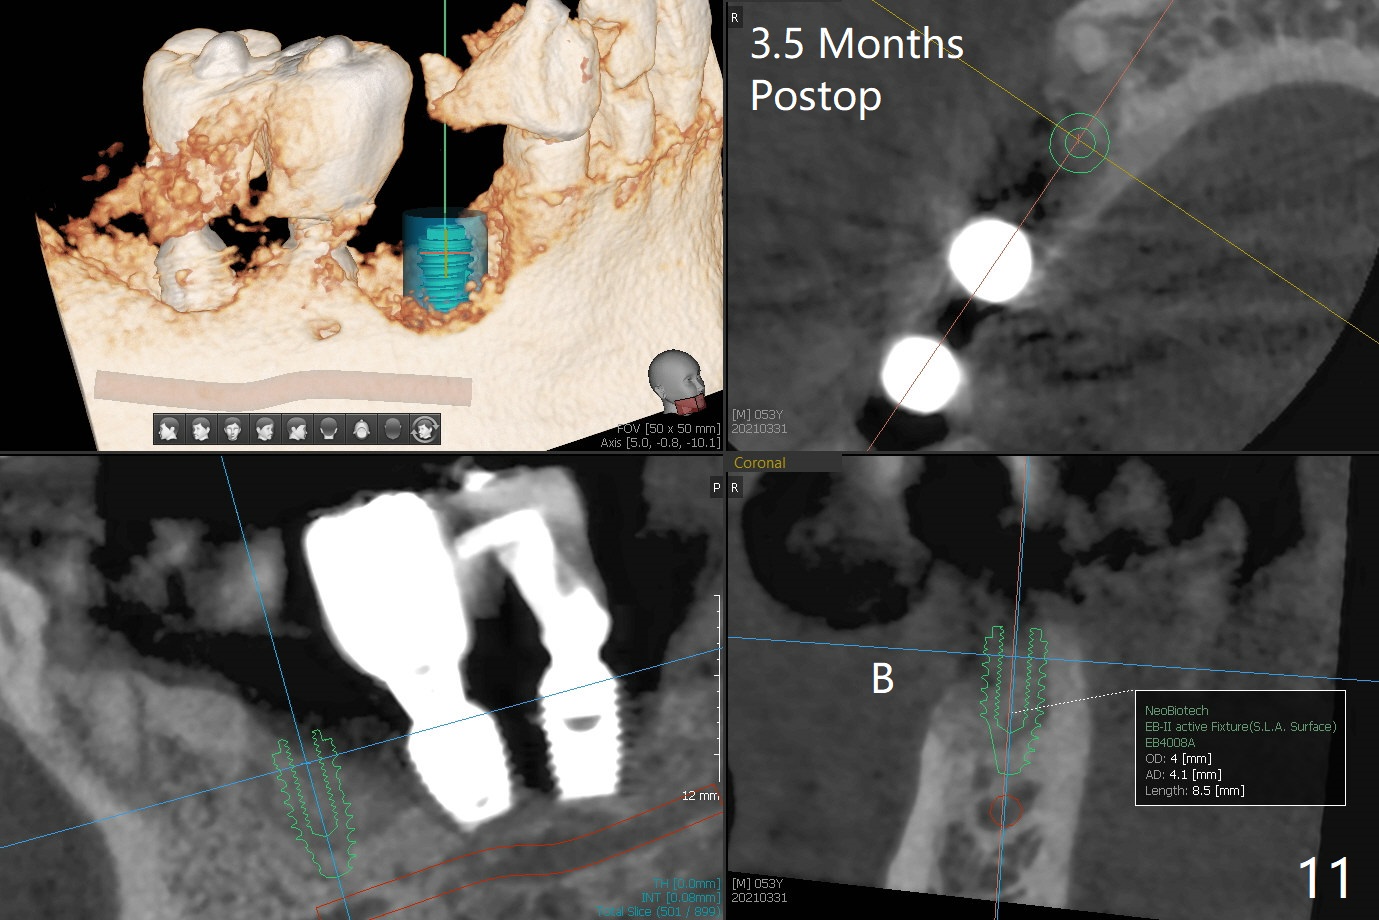

52岁男右下4植体脱落三天回到诊所(图一),植牙创尚未闭锁,顺着开口去除肉芽组织,冲洗,充填皮质骨骨粉(图二,三),颊侧骨板外形恢复(图四,五:*)。重新植入UF植体(5)颊侧还有薄颊侧骨板(图五:>),而6植体周围骨质吸收(图六),植骨好像有希望,植体还在牙槽骨范围,也有利于5植体生存。术后12天伤口愈合(图七)。尽管使用水枪,仍有6植体周围炎,需要治疗(图八)。由于右侧手术,病人不得不用左侧咀嚼,他认为左下4松动,无法挽救。术后3.5个月牙槽嵴和角化龈缩小(图九),需要切开使用导板。术后3.5个月骨粉高度明显下降(图十)。只能植入4x8.5毫米植体(图十一)。